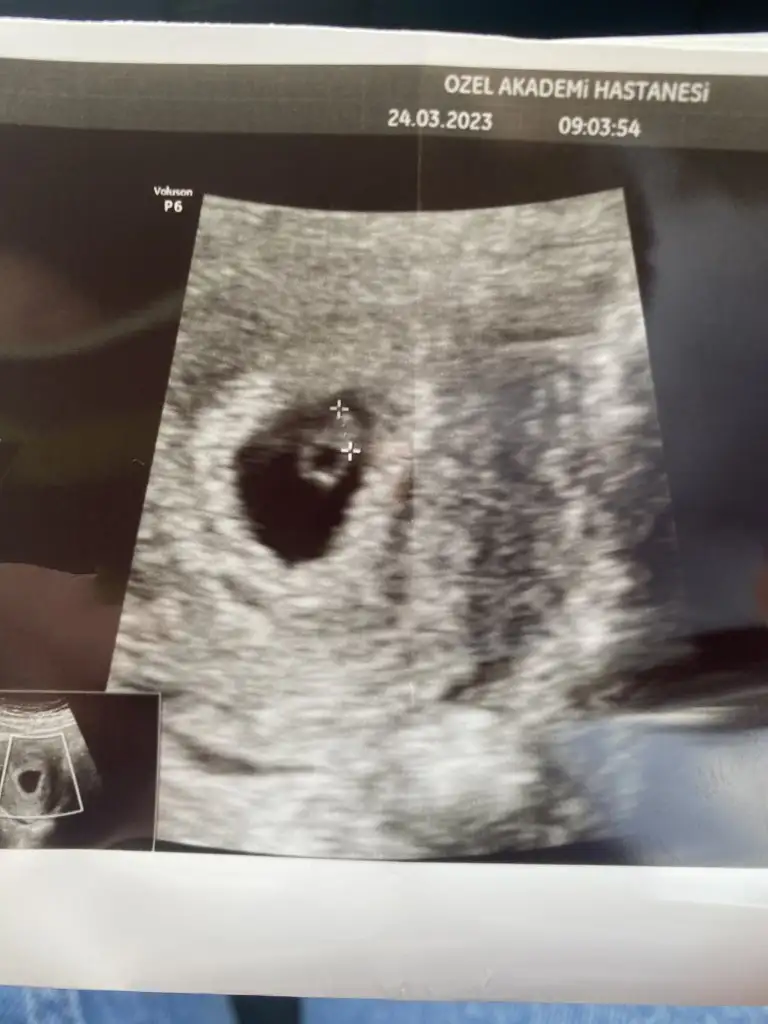

Yaa maşallah bende bugun gıdıcem ama ben 6+0 dayım bir ümit gitmişken belki duyarım dıyorum .Kızlar çok şükür bugün kalp atışını duyduk 6+57.haftadan itibaren cinsiyet tahmini yapan biri vardı keseye göre beni bulsunnnnn

Duymazsanızda canınızı sıkmayın çünkü çok zayıf duyduk bizdeYaa maşallah bende bugun gıdıcem ama ben 6+0 dayım bir ümit gitmişken belki duyarım dıyorum .

Hayırlı olsun canım çok güzel ya rabbim bize de nasip etsin kalp atışlarını duymayı sağlıkla gelsin yavrunKızlar çok şükür bugün kalp atışını duyduk 6+57.haftadan itibaren cinsiyet tahmini yapan biri vardı keseye göre beni bulsunnnnn

salı günü 6+2 de duydum kalp atışını doktorum kese boyu olduğunu sanmıyorum direk kesenin içinde ölçüm yaptı 5 mm dedi sat ım la bebek tam uyumluKızlar haftanıza göre kese boyutunuz kaçtı ? Ve kalp atışını ne zaman duydunuz